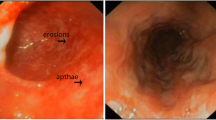

A nine-month-old boy was admitted to our hospital with fever, swelling of the hands, and watery, mucoid, and intermittently bloody diarrhoea (9–10 times/day). Diarrhoea had been present since birth. He had been hospitalized five times due to recurrent lower respiratory tract infections, recurrent otitis accompanied by intermittent arthritis in the hands and/or feet and acute gastroenteritis characterized by watery, mucoid, and intermittently bloody stools. Although he had normal weight gain velocity in the first six months of his life, it was insufficient (100 g/month) in the last three months. His parents were first-degree relatives, and the patient had third-degree relatives with Behçet’s Disease (Fig. 1). The physical examination revealed acute moderate malnutrition (weight and length for age z-score − 2.9 and − 1.5, respectively, and weight for length z-score − 2.8), long and curly eyelashes, oral moniliasis, high palate, an aphthous ulceration on the soft palate, bilateral coarse breath sounds and rhonchi, swelling and tenderness on the 3rd and 4th metacarpophalangeal and proximal interphalangeal joints of both hands. His laboratory tests revealed hypochromic microcytic anemia (Hemoglobin: 8.1 g/dL, mean corpuscular volume: 67 fL), thrombocytosis (669 000/mm3), hypoalbuminemia (3 g/dL), and elevated C-reactive protein [73.9 mg/L (N: 0–5 mg/L)]. Erythrocytes and leucocytes were positive in stool examination. Microbiological tests for cryptosporidium PCR and other diarrheal agents were negative. Sweat chloride test and thyroid function tests were normal. Advanced immunological work-up revealed normal peripheric blood leucocytes, lymphocyte activation with phytohemagglutinin (PHA) and oxidative burst test, except for decreased numbers of CD4+ lymphocytes and natural killer cells (Table 1). Immunoglobulin levels were in normal ranges (Table 1) and specific IgE for cow’s milk and egg yolk were negative. Abdominal ultrasonography and upper gastrointestinal endoscopy were normal, but colonoscopy revealed small aphthous ulcers, hyperemia, oedema, fragility on ileocecal valve and dominantly on distal colonic mucosa. Histopathology revealed mild esophagitis, Helicobacter pylori negative chronic non-atrophic gastritis, mild active colitis with cyrptitis, ulceration and faint cyrpt distortion in distal colonic mucosa (Fig. 2). Cytomegalovirus PCR was negative in blood and tissue examination. Small bowel follow-through radiologic examination was normal. Computed tomography of the chest revealed slight central ground-glass opacity and centriaciner micronodules on the upper lobes of bilateral lungs. Bronchoscopy was normal except for white-coloured mucoid secretion coming from both main bronchi and very mild stenosis of right bronchus intermedius. Bronchoalveolar lavage culture was positive for Klebsiella pneumonia.